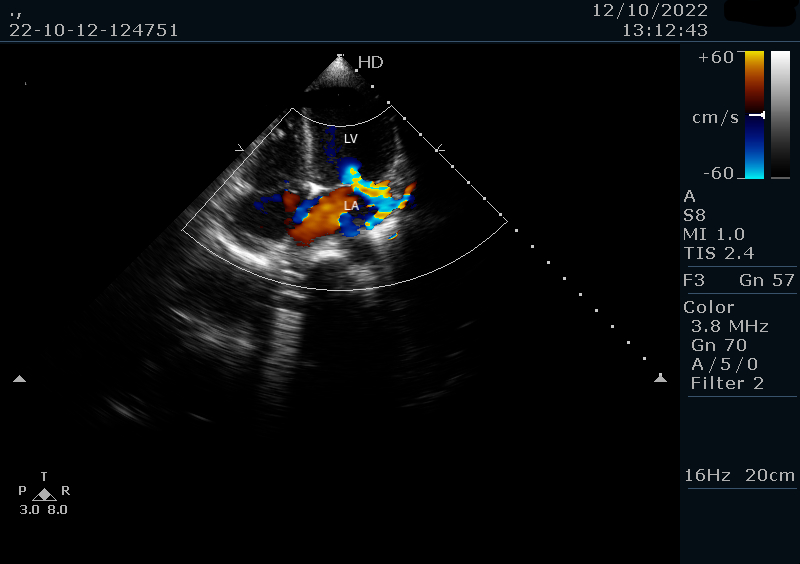

A previously healthy 6-year-old girl from a rural, socioeconomically disadvantaged background presented with a 2-week history of persistent high-grade fever, fatigue, and poor oral intake. She had no prior cardiac or chronic illnesses. Initial management for presumed enteric fever was unsuccessful. On admission, she was febrile (38.5°C), tachycardic (110 bpm), normotensive (90/70 mmHg), and had a grade III/VI pansystolic murmur. The rest of the exam was unremarkable. Labs showed leukocytosis (WBC 17,500/μL) with neutrophilia and elevated inflammatory markers. Chest X-ray and abdominal ultrasound were normal. Transthoracic echocardiography (TTE) revealed a mobile 11 mm vegetation on the anterior mitral leaflet with severe mitral regurgitation (Figure 1). Blood cultures grew methicillin-resistant Staphylococcus aureus (MRSA). IV vancomycin and gentamicin were initiated. No anticoagulation was given. Cranial CT and neurologic assessment were normal. After 14 days, repeat TTE showed a reduction in vegetation size to 8 mm. She remained afebrile and clinically improved. Antibiotics were continued for 6 weeks. A follow-up echo 4 weeks post-discharge showed complete resolution of the vegetation with persistent moderate mitral regurgitation (Figure 2). No embolic or neurologic events occurred. At 3-year follow-up, TTE confirmed no vegetation recurrence and stable MR (Figure 3) .